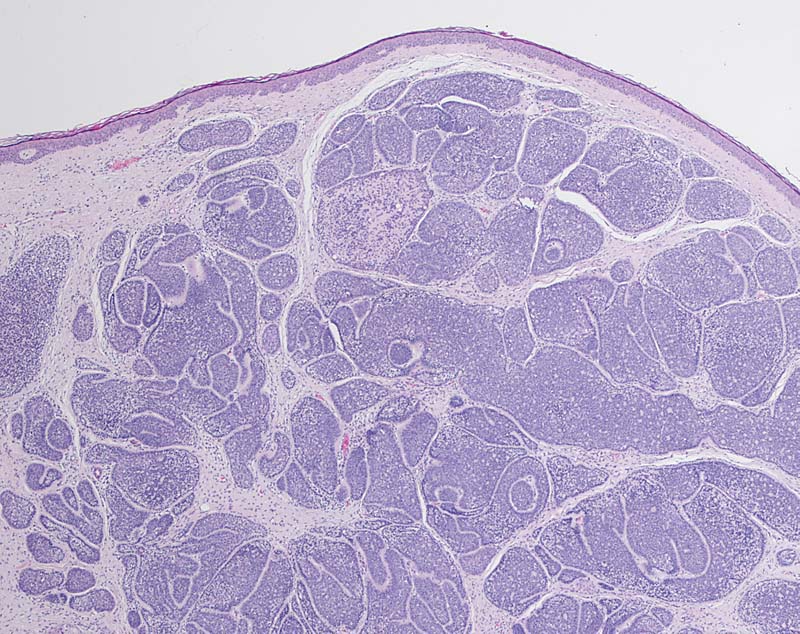

Zylindrom

benigner Tumor

Haut, Kopf

Dermaler Tumor ohne Beziehung zur Epidermis. Ovale und polygonale mosaikartig angeordnete Tumorzellnester werden eingefasst von von hyalinen Bändern (Typ IV Kollagen). In der Peripherie kleine stark basophile Tumorzellen mit angedeuteter Palisadierung. Im Zentrum etwas grössere blassere Zellen und kleine Lumina.

Multiple Zylindrome der behaarten Kopfhaut

Multiple Tumoren werden autosomal dominant vererbt und können im Kopfbereich konfluierende Knoten bilden (sog. Turbantumor).

Histologie

25